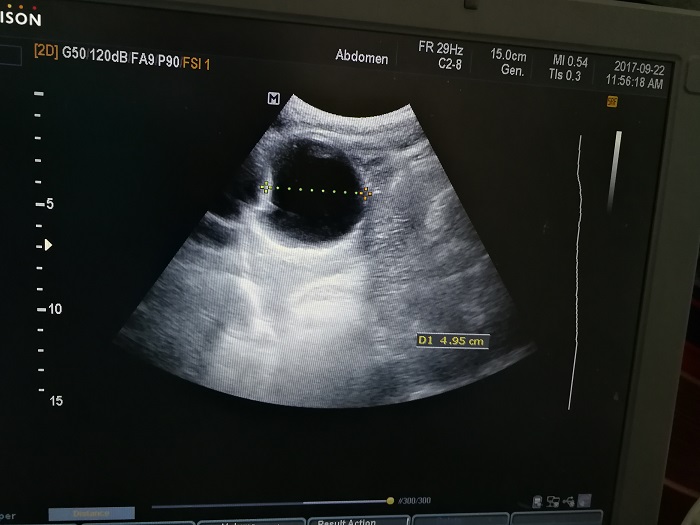

扎西(化名),男,15歲,包蟲病篩查陽性,牧區(qū)孩子,家里有牦牛20頭、羊200只,狗1條,牛羊自家屠宰,飲用河水。

●革吉縣初級中學(xué)篩查點(diǎn) · B超現(xiàn)場圖片

除了包蟲病篩查外,連續(xù)三天的學(xué)校體檢我醫(yī)療隊發(fā)現(xiàn)腎積水、腎囊腫、腎結(jié)石的學(xué)生患者較多,我們將體檢到的相關(guān)臟器疾病同時間反饋給了班主任,讓他們密切觀察病情,及時通知家長。劉冬梅醫(yī)生建議,學(xué)校要組織學(xué)生多飲水,同時多加觀察本地水質(zhì)情況。

本次篩查,革吉縣初級中學(xué)共篩查學(xué)生498例,陽性3例,疑似2例。